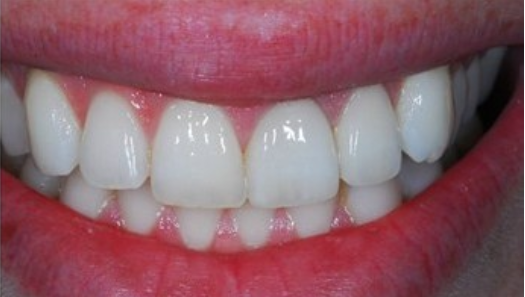

요즘은 신논현역 치과에서는 대부분 임플란트 치아의 보철물은

지르코니아를 사용합니다.

지르코니아는 본인의치아색과똑같이만들수가있어 심미적으로 타 재료들보다 월등히 뛰어납니다.

단단하여 깨지는일이 거의없어 금이나 pfm보다는대개 30-40만원더비싼 편입니다

지르코니아는 앞니에도 어금니에도 미관상 자연치아와 크게 다르지 않습니다.